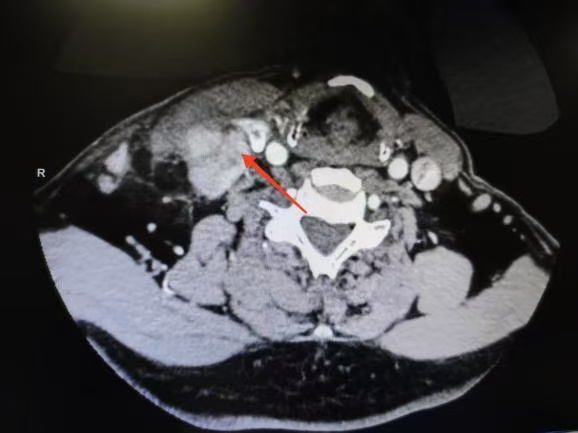

CT箭頭所示:側(cè)頸區(qū)轉(zhuǎn)移淋巴結(jié)

荊楚網(wǎng)(湖北日報(bào)網(wǎng))訊(通訊員 楊青青 沈浩元 )近日,孝感市中心醫(yī)院甲狀腺乳腺外科成功為一名67歲男性患者實(shí)施了高難度甲狀腺癌根治手術(shù)。該患者因頸部突發(fā)硬塊4天就診,經(jīng)檢查確診為雙側(cè)甲狀腺乳頭狀癌伴右頸側(cè)區(qū)多發(fā)淋巴結(jié)轉(zhuǎn)移,術(shù)中進(jìn)一步發(fā)現(xiàn)腫瘤已侵犯包繞喉返神經(jīng),側(cè)區(qū)轉(zhuǎn)移淋巴結(jié)亦侵犯頸內(nèi)靜脈,病情復(fù)雜且兇險(xiǎn)。